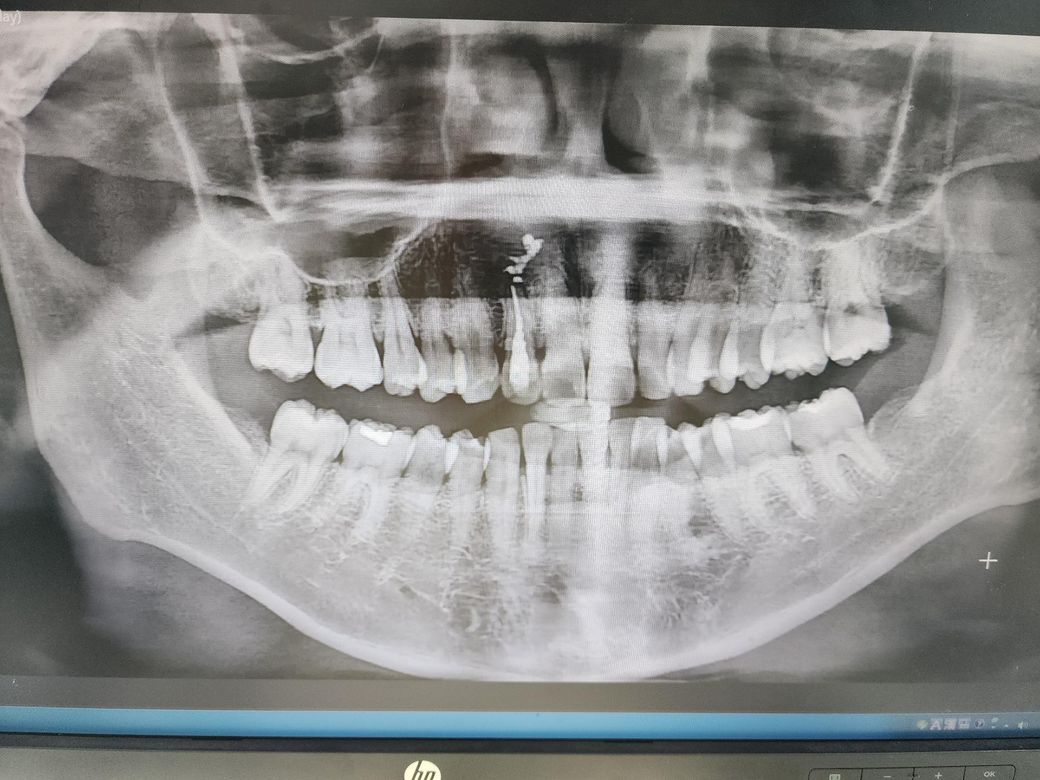

어금니 잇몸 퇴축 심한가요?? ?????

유독 맨끝 어금니쪽 워터픽으로 하면 아픕니다. 혹시 잇몸퇴축이 심한가요?? 최근에 잇몸치료했는데 별말씀없긴했어요 ㅠㅠㅠㅠ

잇몸퇴축이 심한 편은 아닙니다. 다만 큰어금니 2개끼리 단차가 있어 다른 부분에 비해서 비교적 음식물이 잘 끼이고, 닦기도 쉽지 않아 잇몸이 좀 더 잘 붓는 것 같습니다. 워터픽보다는 치실이나 치간칫솔 등 직접적으로 음식물과 치태를 제거할 수 있는 용품을 사용하시면 좋을 것 같습니다.

잇몸 퇴축은 그닥 심하지 않습니다

어금니 이전에 떼운부위 하방 충치 의심되니 치근단 엑스레이 찍어보시기 바랍니다